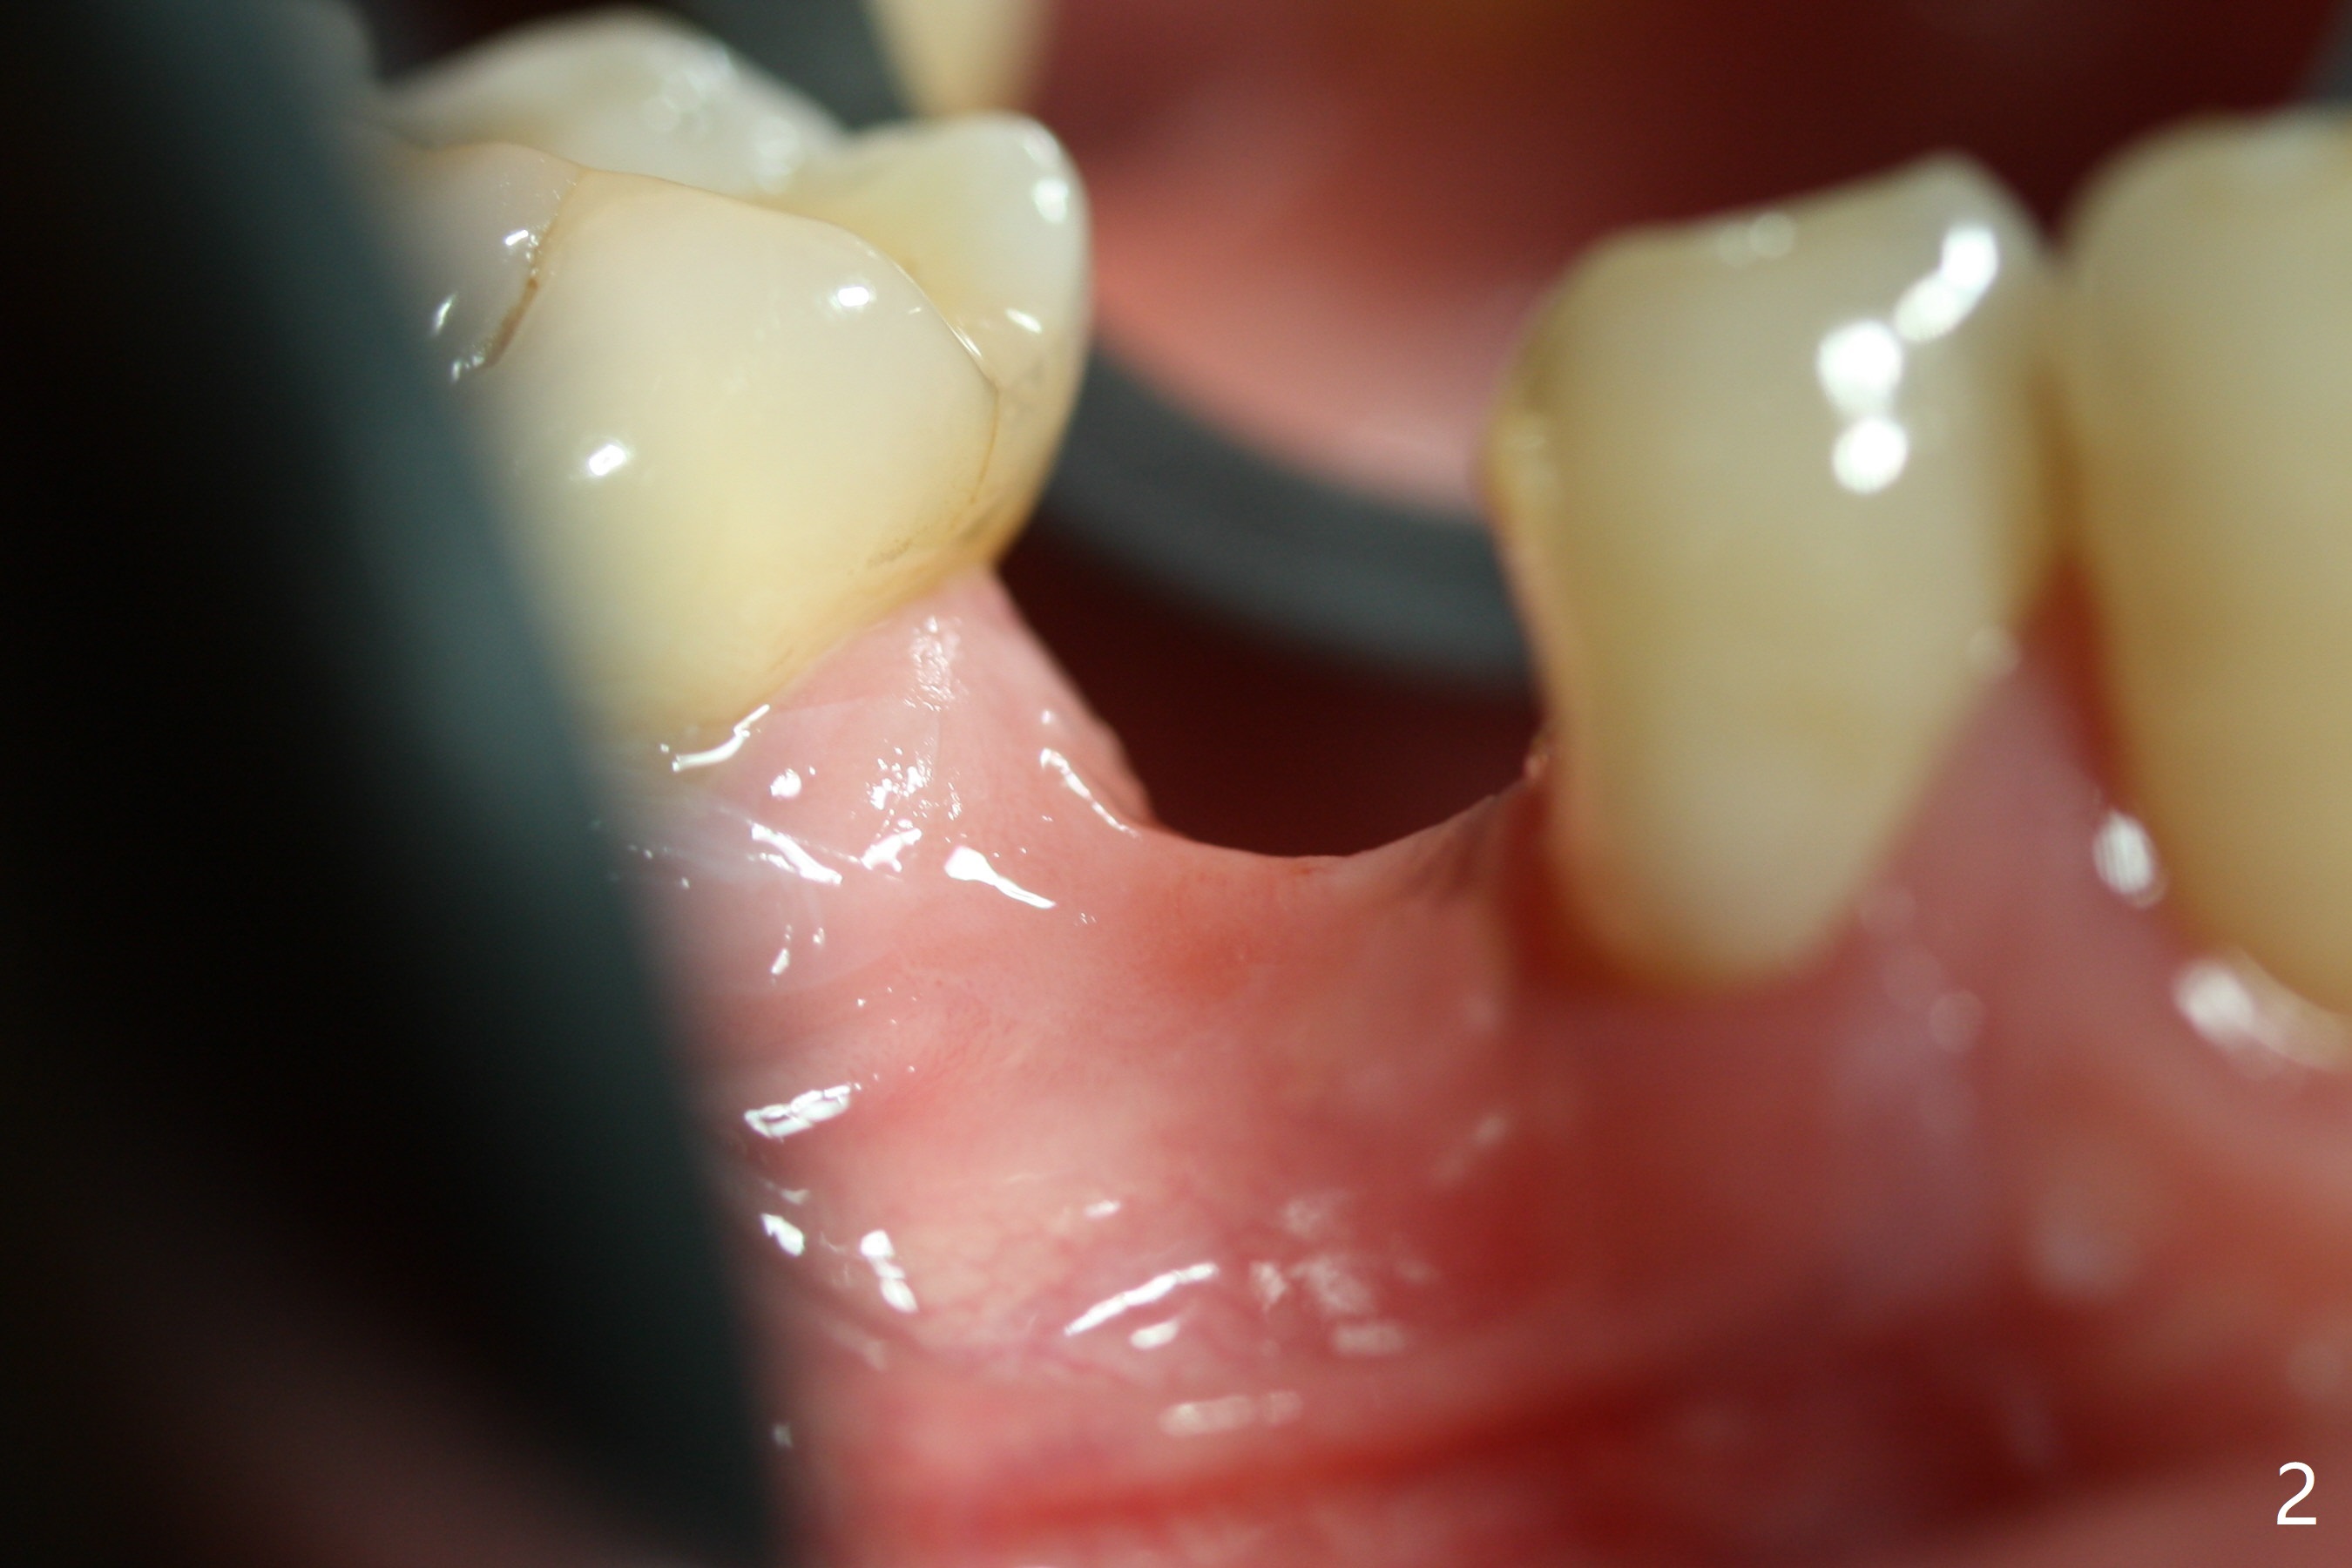

The base of the edentulous ridge at #29 looks wide (Fig.1), but the most coronal portion is the thin soft tissue (Fig.2).  It appears that there has been bone resorption since extraction.  The initial osteotomy depth is 11.5 mm (Fig.3).  Since the Mental Loop seems to be nearby, the depth of subsequent osteotomy (3 mm) remains the same (Fig.4).  Although the final depth of osteotomy is 13 mm, the implant placed is short (3.8x11.5 mm, Fig.5,6), as compared to the immediate implant (3.8x18 mm) at the contralateral side (#20).  There is mild bone resorption mesially 4 months postop (Fig.7).  The crown is loose (poor osteotomy position, guide necessity) 7 months post cementation immediately prior to 18 cementation, although there is no gross bone losss 1 year 7 months post cementation (Fig.8).